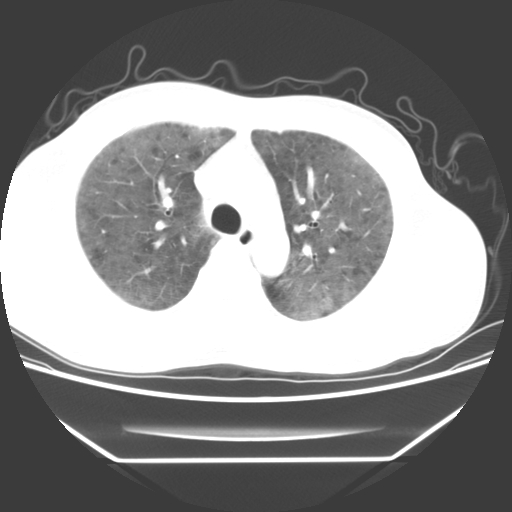

病人55岁,咳嗽,胸闷

忘了传病史了,病人55岁,咳嗽,胸闷

两肺部呈“毛玻璃”状改变,原因待查考虑感染性病变

病人是否发烧,两肺“磨玻璃”影,其间见空气支气管征和碎路石征。考虑肺泡蛋白沉着症。

两肺广泛对称磨玻璃样影,密度不均,考虑机遇性肺部感染。

双肺弥漫磨玻璃样病变,病史很重要。有感冒或发烧史,甲流不除外。无发烧可考虑肺泡蛋白沉积,但肺泡蛋白沉积边缘往往较清晰,与正常肺组织分界清晰

两肺弥漫间质性病变,考虑肺泡蛋白沉着症。建议进一步检查。

此病人我并没有见到,病史没有得到更详细,但此病人据说有发低热,请教各位老师,此病人像不像卡氏肺囊虫肺炎